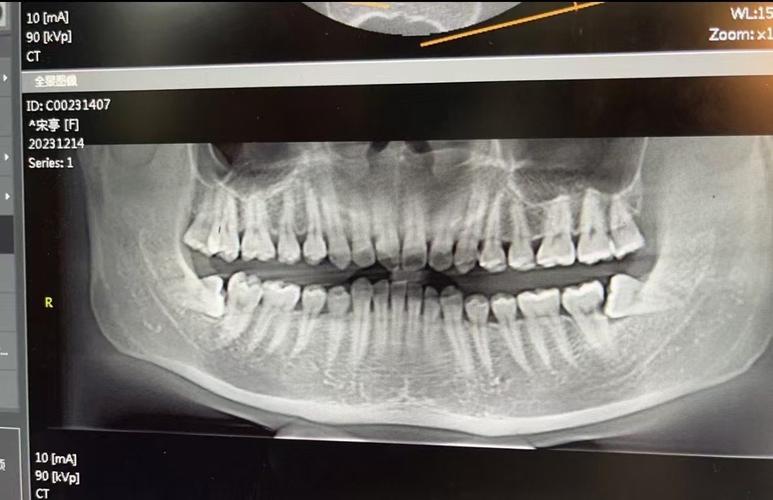

| CBCT(锥形束CT) | 三维重建口腔结构,可任意层面观察牙根与骨壁关系、埋伏牙位置、骨量不足区域、上颌窦及神经管位置 | 复杂病例(如埋伏牙牵引、骨性畸形术前评估、种植支抗植入) |